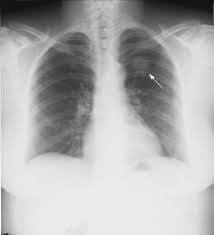

Με τον όρο οζίδιο ή όζος, εννοούμε ένα υπέρπυκνο ιστό σε σχέση με το υπόλοιπο πνευμονικό παρέγχυμα το οποίο εντοπίζουμε με κάποια απεικονιστική εξέταση όπως ακτινογραφία ή αξονική τομογραφία θώρακος.

Ένας όζος παρατηρείται τυχαία κάθε 500 περίπου ακτινογραφίες θώρακος. Μπορεί να είναι ένας οπότε ονομάζεται μονήρης όζος ή πολλαπλοί.

Είναι πολύ σημαντικό να επιβεβαιωθεί αν ένα οζίδιο είναι καλοήθες ή είναι σε πολύ αρχικό στάδιο κακοήθεια.